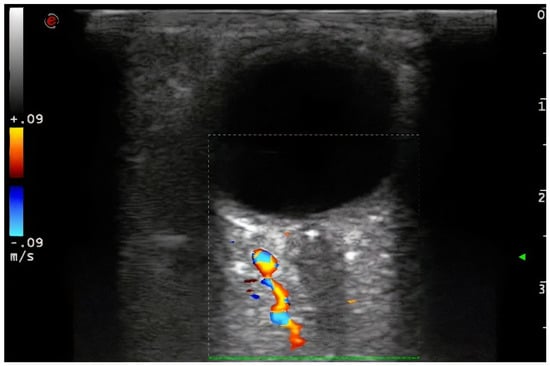

Demographic variables and vascular risk factors were collected. Orbital ultrasound findings were obtained using a 3–9 MHz linear probe (Esaote MyLab70 and My Lab9, Esaote, Milan): the absence of color and pulsed Doppler signal in the peripapillary portion of the CRA (diagnosis of CRAO) (Figure 1) and the presence of hyperechoic material in the retrobulbar circulation of the optic nerve (spot sign) were explored (Figure 2).

Figure 1. The absence of color and pulsed Doppler signal in the peripapillary portion of the CRA (diagnosis of CRAO). 3–9 MHz linear probe (Esaote MyLab70 and My Lab9, Esaote, Milan).